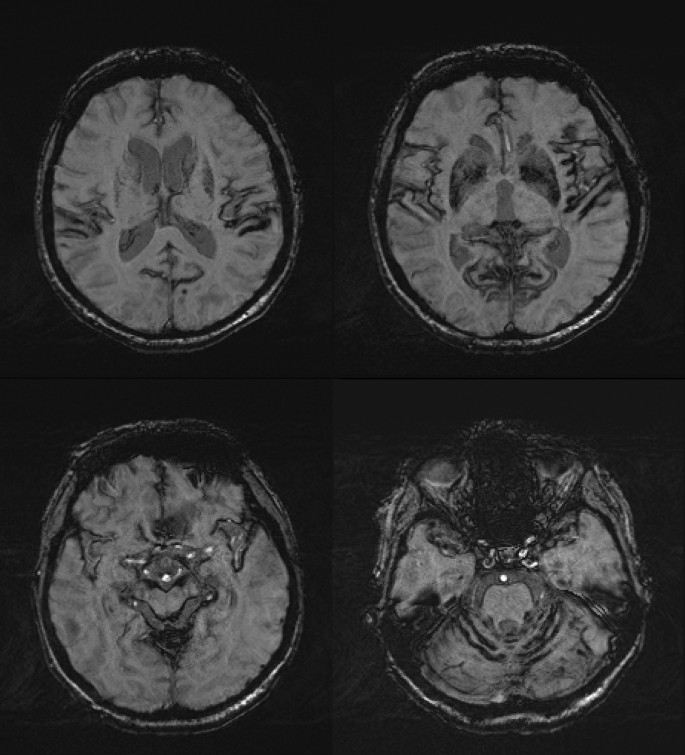

Magnetic resonance imaging (MRI) of the brain with susceptibility-weighted sequences finally showed diffuse bilateral superficial siderosis with bitemporal, bi-insular, and cerebellar emphasis (Fig. 1). No overt reason could be determined for this finding. We were unable to perform conventional angiography because of severe arteriosclerosis, elongation, and tortuosity of aorta and supra-aortic arteries. MRI of the spine did show hemosiderin remnants on the height of the first lumbar vertebra and the ankylosing spondylitis.